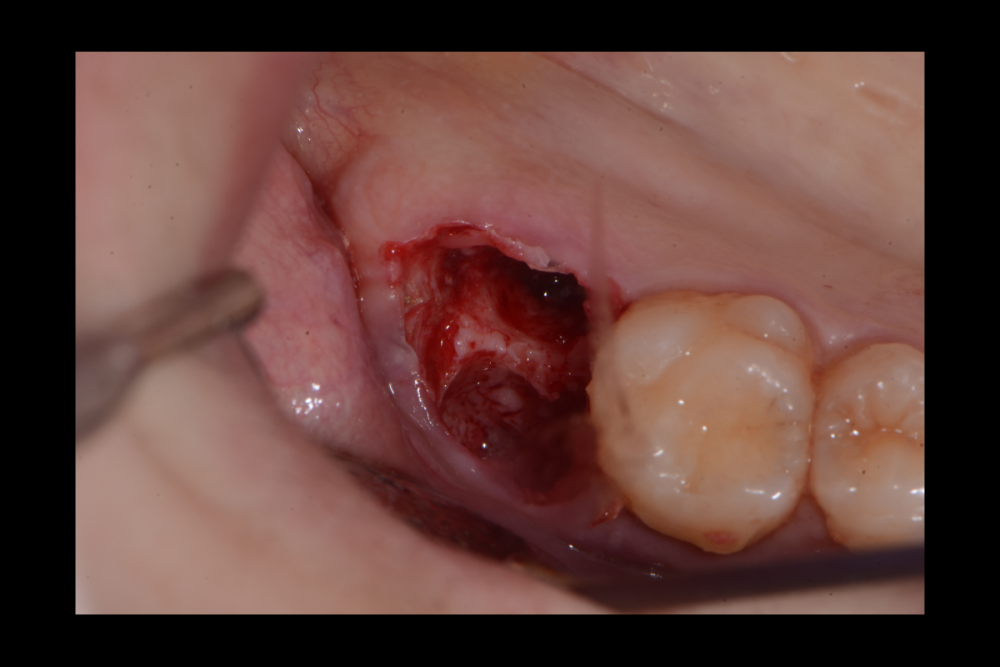

Карен Аванесов Опубликовано 20 сентября, 2021 Поделиться Опубликовано 20 сентября, 2021 (изменено) одномоментной установки имплантата, без вторжения в верхнечелюстной синус, регионарная мягкотканная пластика, выгодная ортопедическая ангуляция, не выгодной небной лунки. Пустоты заполнены губкой дигестол, дополнительная герметизация ликвидам. Мой только хирургический протокол, пациент реферативный. Время работы от удаления до имплантации 40 минут, ожидание до протезирования 3 месяца. Кейс посвящаю одноглазому и зеленому хулигану, любителю пива и девок, не знаю куда он делся, но пусть не грустит, все будет хорошо! Изменено 20 сентября, 2021 пользователем Карен Аванесов 10 1 1 Ссылка на комментарий